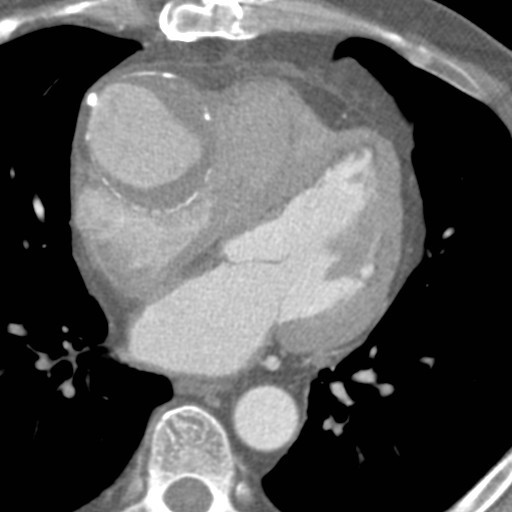

67-year-old male with history of prosthetic aortic valve stenosis, now with dyspnea on exertion and lower extremity swelling

Vertical retrosternal opaque stripes representative of possible pericardial effusion (“oreo cookie sign”).